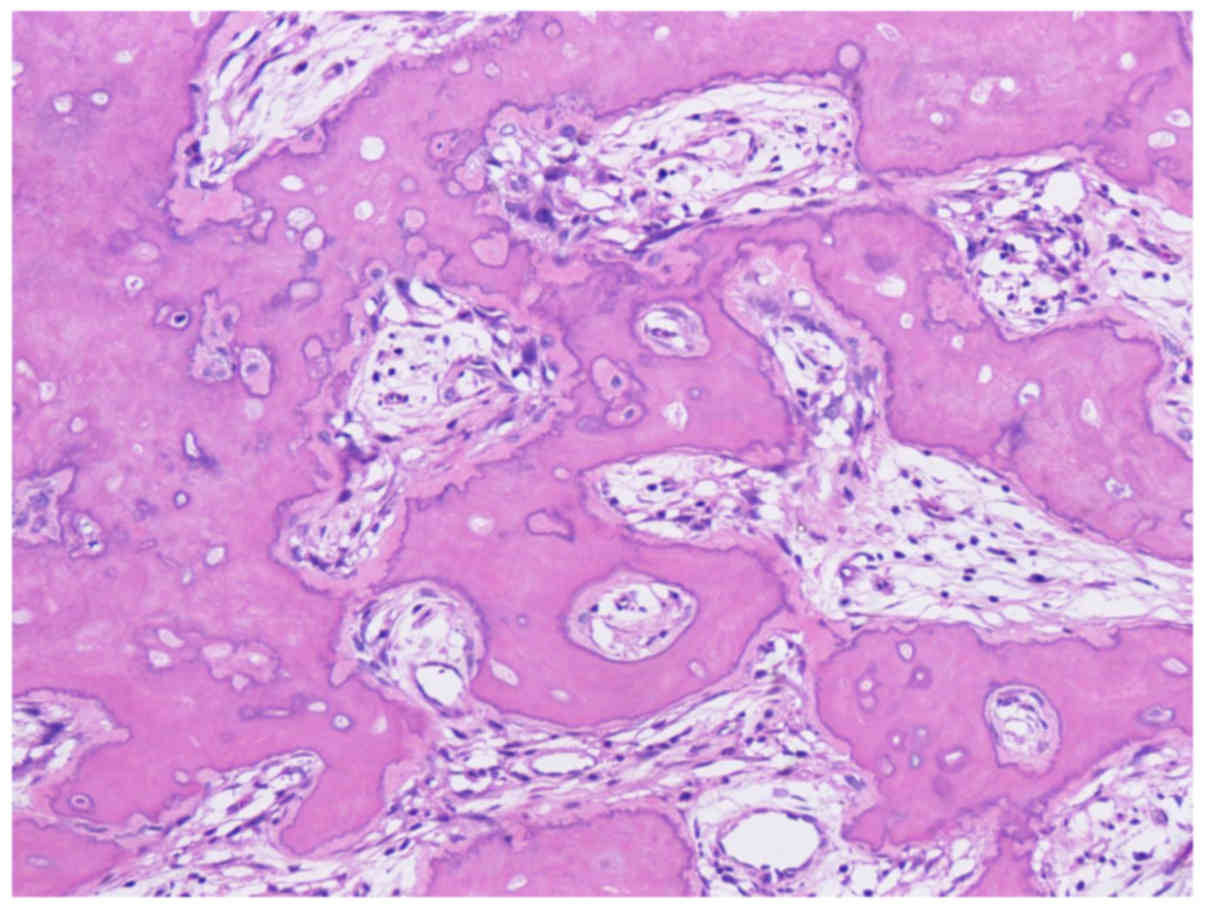

dissection (April 2016). Histopathological examination revealed

‘OS, post-therapeutic state’, and the surgical margins were

negative. Surgical materials obtained by segmental resection of the

right mandible showed a lot of newly formed woven bone attached to

the existing mandibular bone, and most of the osteocytes and tumor

cells were dead due to chemotherapy. Namely, tumor showed

characteristics of bone formation on the surface of mandibular bone

(Fig. 4). No tumor cell was found in

the bone marrow. According to these findings, the initially

obtained biopsy, clinical and radiological findings, it was

suggested that a part of tumor cells showed high-grade atypia,

although most of the tumor mass showed abundant bone formation,

which arose from the bone surface. Therefore, we considered two

possible diagnoses: high-grade OS of the mandible or parosteal OS

with partial dedifferentiation to high-grade OS (18). However, because of the death of tumor

cells due to chemotherapy, we could not determine which diagnosis

was correct. There was no indication of metastasis to the lymph

nodes. Postoperative chemo/radiotherapy for OS was not performed.